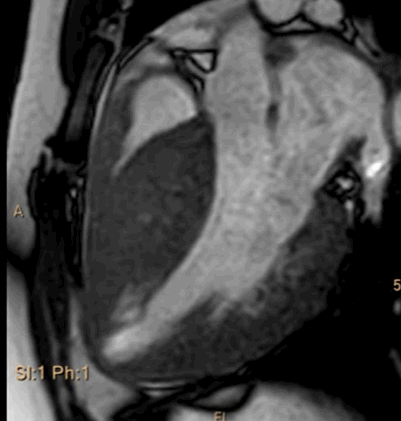

- It is a temporary circulatory support device ideally used prophylactically in high-risk situations

- It takes a minimum of 20 to 30 mts (If it’s in ready mode) to insert the AV ECMO , Further, there must be some cardiac activity till the ECMO takes over.

“Let me go little deeper into the hemodynamics of ECMO, even if it is inserted on time, ECMO doesn’t support coronary circulation much, (the one that matters most in the failing heart) ECMO circuit that brings oxygenated blood from below upwards in descending aorta. This stream may not reach the aortic root as it has to competes with ventricular contractions however feeble it may be” (Ref 1)

We must realize ECMO is not a new breakthrough technology. It’s a 50-year old concept, that was used primarily in infants with respiratory failure. (VV ECMO) In the complex high-risk interventional cardiology field, it has a different purpose. It gives the aggressive players a little more time to try their luck of reperusing a failing heart.

All these circulatory assist devices Like ECMO, Impella, IABP help to support the heart before a cardiac standstill. Ideally, we may use them prophylactically ( in situ and ready to fire) It has helped save lives especially in pre and post-transplant hearts However, it’s too complex a procedure to be relied upon after unanticipated Ischemic cardiac arrest. We can expect, It might get miniaturized and user friendly soon.